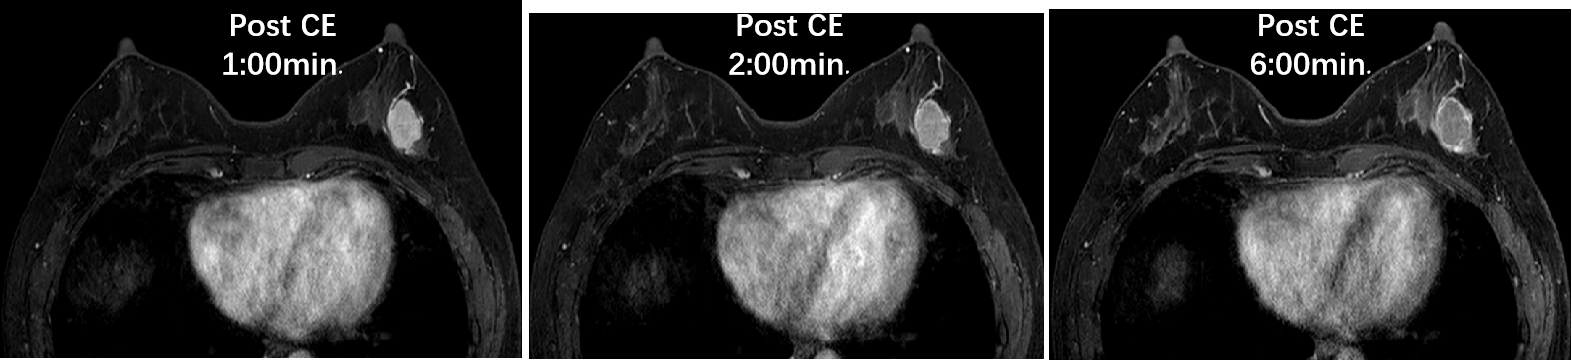

乳腺成像方向

高分辨率图像让肿瘤与正常乳腺组织更容易分辨,通过动态增强、波普、时间信号强度曲线及ADC值评价肿瘤良恶性符合率更高,其敏感度和准确度明显高于其他检查方法。

08乳腺